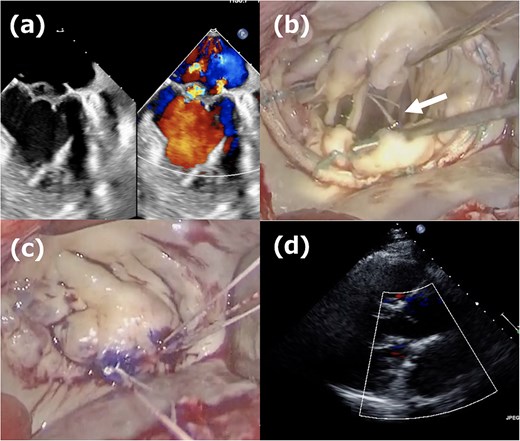

A 52-year-old man presented with chest discomfort on exertion. Transthoracic echocardiography (TTE) revealed severe MR due to a large prolapse of the A2 segment (Fig. 1a). Minimally invasive mitral valve repair was performed through right-sided small thoracotomy. The prolapsed A2 segment was treated with four 22-mm-ePTFE loops (CV4, Gore-Tex, W.L. Gore & Associates, Flagstaff, AZ) attached to the anterior papillary muscle. These loops were fixed to the A2 segment with 5/0 polypropylene sutures (Prolene, Ethicon, NJ) as shown in Fig. 1b. For annuloplasty, a 36-mm CG-Future band (Medtronic, MN) was applied (Fig. 1c). Intraoperative transesophageal echocardiography (TEE) and postoperative TTE showed no residual MR (Fig. 1d), and the patient was discharged on postoperative day 8. At a routine outpatient follow-up clinic 3 weeks later, a severe systolic murmur was detected, and TEE revealed a moderate MR. Partial prolapse of the A2 segment, which was treated at the first operation using the loop technique, was observed (Fig. 2a), and the lactate dehydrogenase level was 1599 U/L, indicating hemolysis. Although the patient remained asymptomatic, reoperation was recommended due to his relatively young age.

First operation images. (a) Severe mitral regurgitation caused by A2 prolapse. (b) Intraoperative image showing the placement of four 22-mm ePTFE loops fixed to the A2 segment with 5/0 polypropylene sutures. (c) The 36-mm CG-future band (Medtronics) was applied for mitral annuloplasty. (d) One week postoperative echocardiogram showing no residual mitral regurgitation.